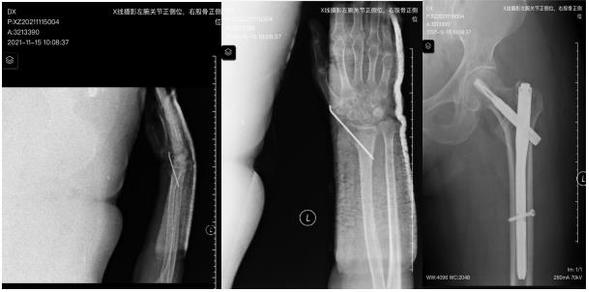

术后X线

患者高血压病史3年,曾有胸壁结核病史。骨外三科医生考虑该患者高龄,老年髋部骨折卧床时间长、并发症多等问题,经讨论决定早期为患者进行手术治疗,但考虑老年患者多处骨折切开复位损伤较大,出血较多,术后患者恢复慢,甚至出现因手术创伤导致患者其他一些应激性疾病发生,最终经科室医生与骨外三科主任桑梓英讨论后拟行闭合复位内固定术,与患者家属沟通后,家属同意该手术治疗方案。11月12日,行手术治疗,手术过程顺利,左腕部无切口,左髋部切口长约4cm,该病人两处骨折分别予以闭合复位微创固定,未选择切开复位固定,闭合复位固定技术可以让病人早期活动,缩短住院日,该患者术后5天即出院,减轻了患者的经济负担,使患者得到快速恢复,符合快速康复理念(ERAS)。